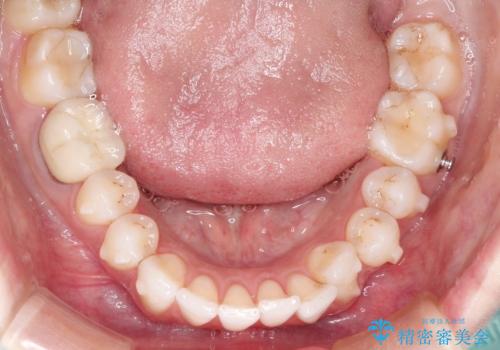

インビザラインによる非抜歯での八重歯の矯正

- 左上の八重歯と、上の歯のがたつきを主訴に来院されました。

上の奥歯を後方に移動させてスペースを作るのと、歯と歯の間をわずかに削り歯を並べる計画としました。

非常に強力的な患者様であったので、上下の正中も合わせ、ガタガタも改善することができました。